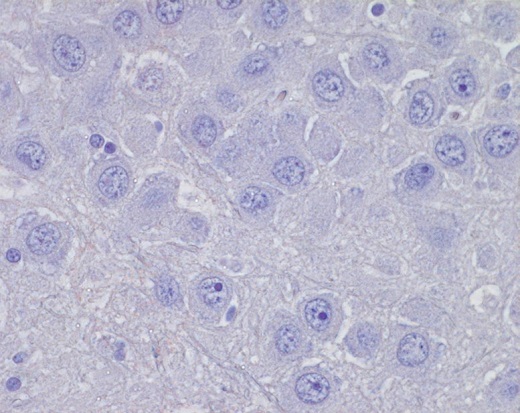

Direct rapid immunohistochemical test (DRIT)

The DRIT for rabies functions similarly to the DFA test in detecting the presence of rabies virus antigen in animal tissues. Like DFA, DRIT relies on observing rabies virus-expressed proteins in infected nervous system tissues.

- Brain tissue is ideal due to its high concentration of rabies antigen.

- Other innervated tissues may have antigens, but they are less accurate at detecting rabies when compared to brain tissues.

- The key component of the DRIT test is rapid immunohistochemical staining with anti-rabies antibodies.

- These antibodies are labeled with a chromogenic marker and when incubated with suspect tissue, the marker binds specifically to rabies antigen.

- Excess antibodies are then washed away, and areas containing rabies antigens appear in color under a light microscope.

- The absence of staining indicates the absence of rabies virus

Like DFA, DRIT boasts high sensitivity and specificity. It has been thoroughly evaluated by international, national, and state health laboratories.

Immunohistochemistry (IHC)

IHC methods are sensitive and specific for the detection of rabies virus antigen in formalin-fixed tissues. IHC testing is more sensitive and specific than histologic staining methods, such as hematoxylin and eosin (H&E) and Sellers stains.

- Brain tissues fixed in formalin must first be processed by routine histologic methods, embedded in paraffin, and sectioned to formalin-fixed paraffin-embedded slides.

- Rabies virus antigen is detected using specific anti-rabies monoclonal or polyclonal antibodies.